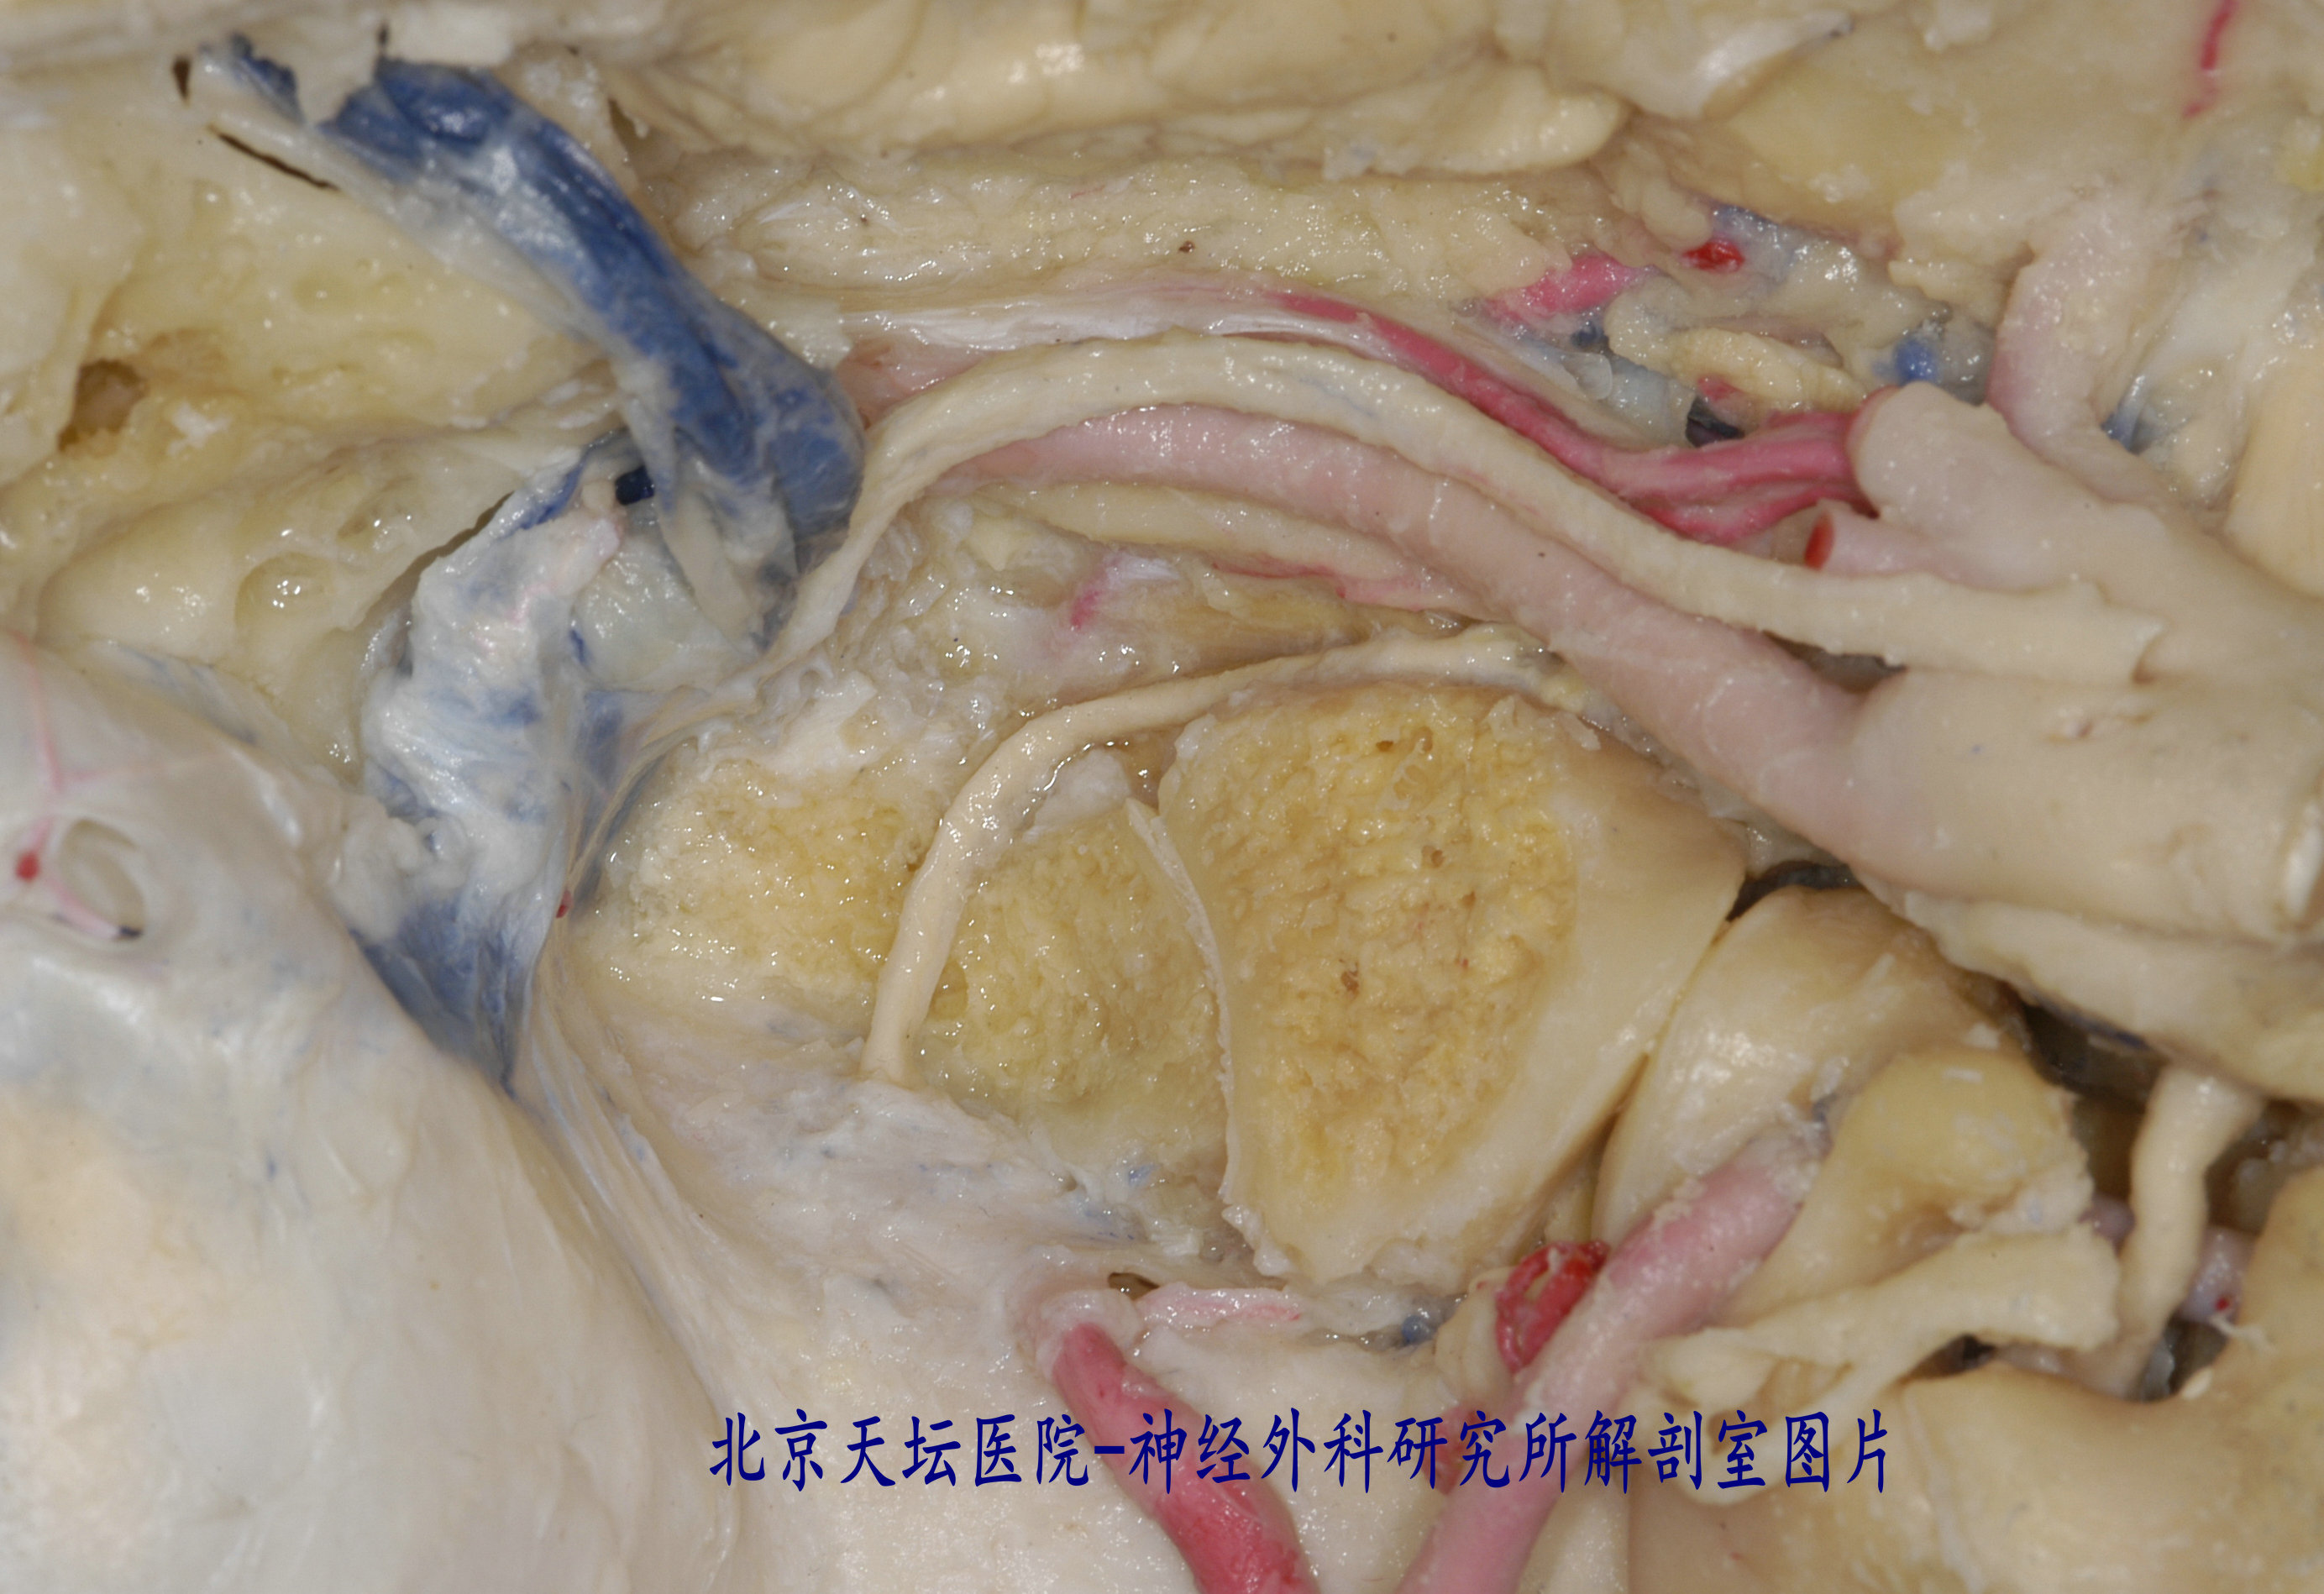

这个是手术过程,实践中感觉舌下神经管鞘瘤越小,越难暴露。